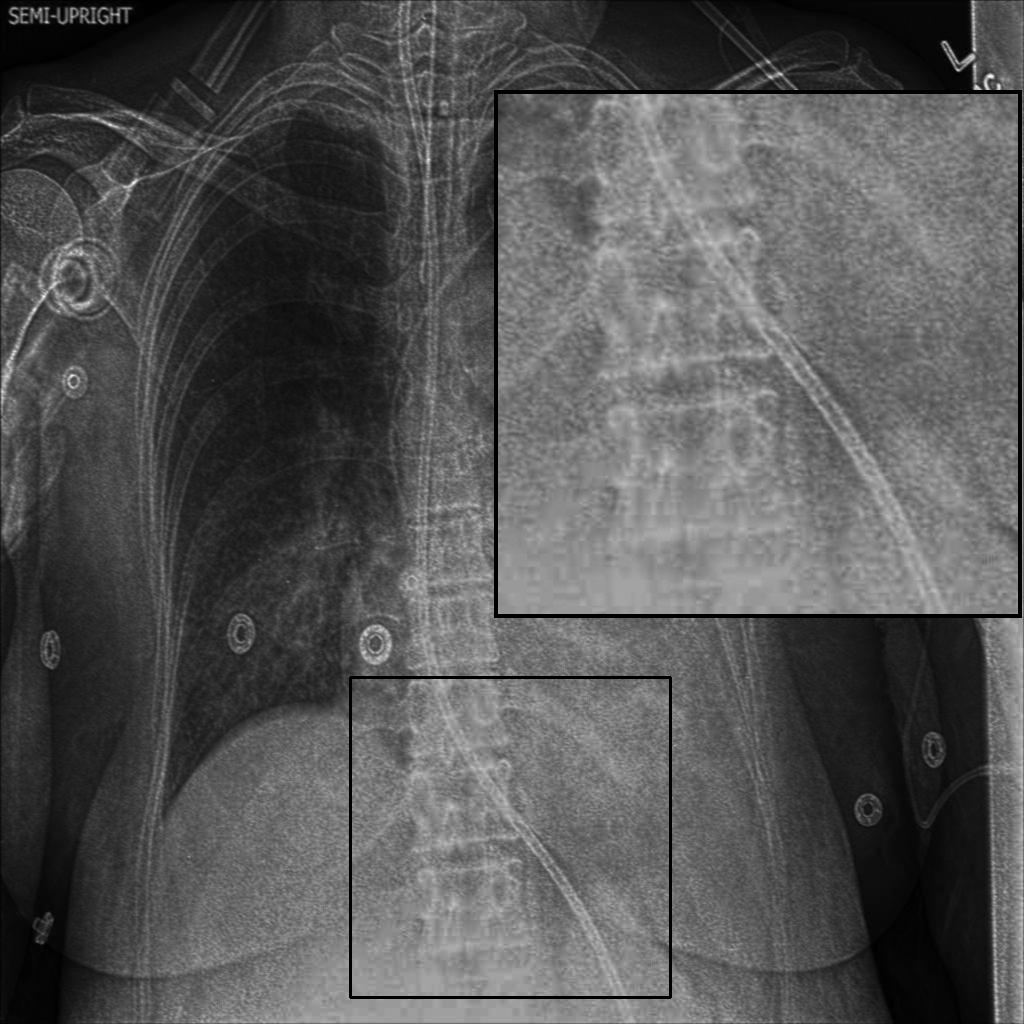

4.5 A Visual Assessment

Fig. 4 presents representative visual examples demonstrating the superiority of our method in enhancing vertebral contrast compared to several traditional and learning-based image enhancement techniques. The first and second columns show results from the JSRT and Montgomery County Chest X-ray datasets, while the third and fourth columns display results from the NIH ChestX-ray14 and CheXpert datasets. Across all datasets, the highlighted regions of interest (ROIs) emphasize the spinal areas, where fine structures and subtle details are critical for diagnostic assessment. Our method, XVertNet, consistently reveals clearer and more distinct spinal structures without introducing notable artifacts, preserving both global and local anatomical information. In contrast, traditional methods such as CLAHE [7] and Farbman et al. [19] often fail to enhance these subtle features effectively, either producing over-smoothed results or excessively sharpening noise. Similarly, learning-based methods such as ZSSR [43] and Madmad et al. [68] exhibit difficulties in generalizing across different datasets, leading to either insufficient enhancement or visible artifacts. Zero-DCE [33], although effective for natural images, struggles to adapt to the uniform and low-contrast nature of medical X-rays and was not able to supply clear enough contrast-enhanced vertebral structures.

These visual comparisons underline the clinical relevance of our approach. XVertNet successfully enhances diagnostically important structures, particularly in challenging anatomical regions like the spine, where competing methods either distort the features or fail to sufficiently reveal them. This highlights the value of integrating targeted enhancement strategies that are specifically tailored to the unique characteristics of medical imaging data.